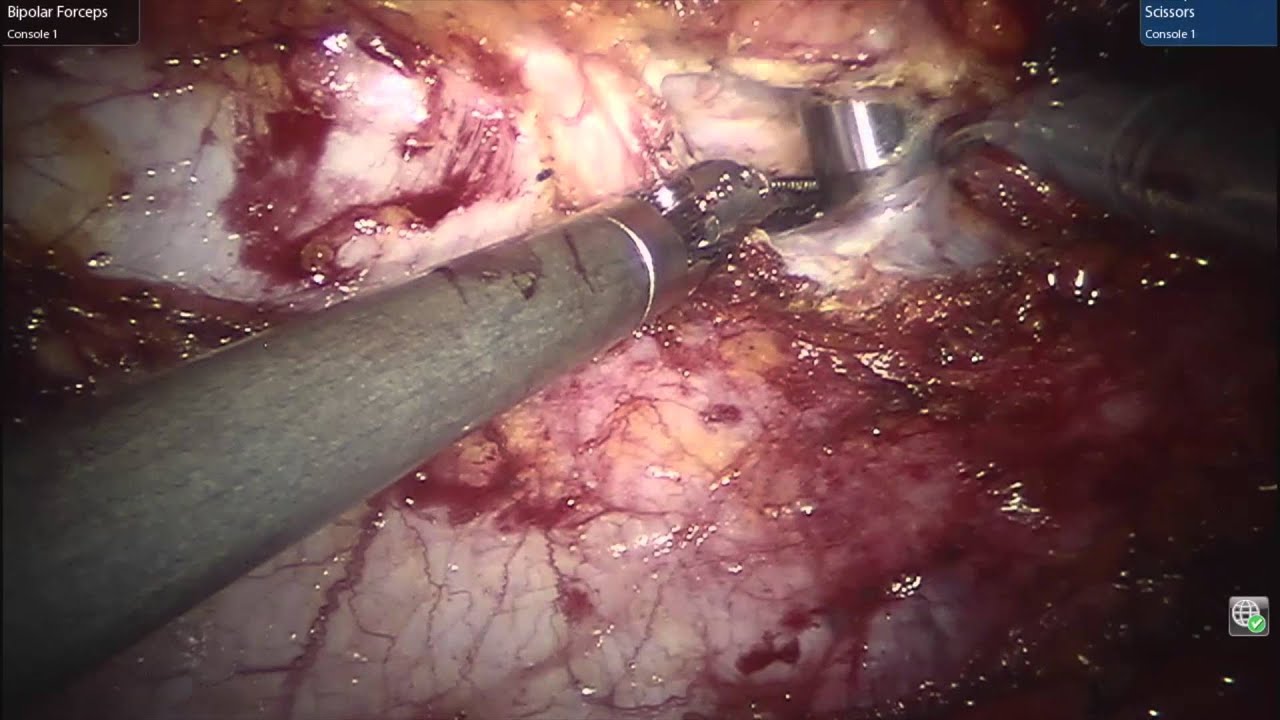

video phone é a continuação de telephone Robotic Retrorectus Transabdominal Approach

camera iphone 8 plus apk Robotic Transversus Abdominus Release (TAR)